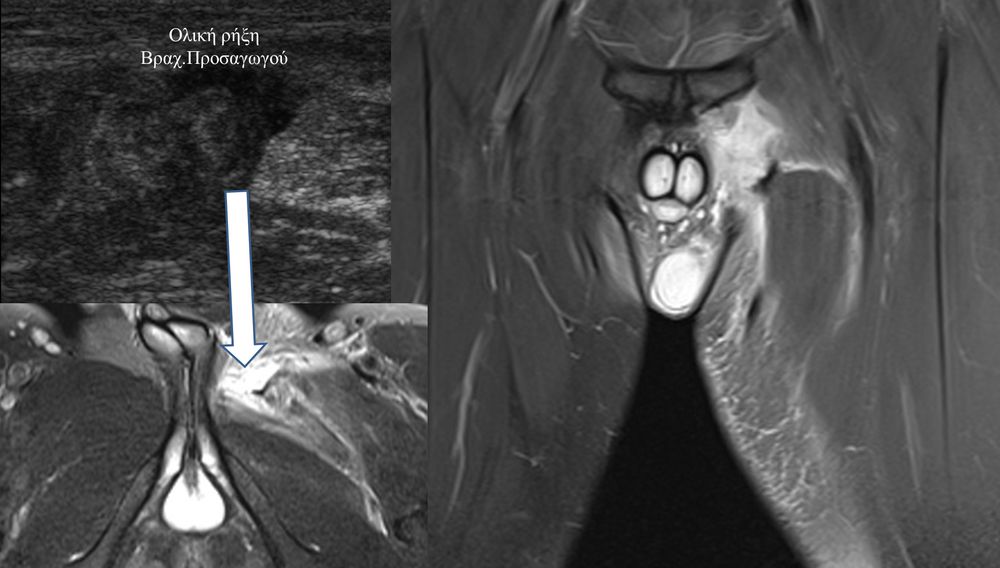

Είναι μια νέα μέθοδος που χρησιμοποιεί υψηλής ευκρίνειας υπερήχους για τη διάγνωση μυοσκελετικών παθήσεων που αφορούν τένοντες, μυς, συνδέσμους, νεύρα και περιφερικές αρθρώσεις. Η μέθοδος αναπτύχθηκε τα τελευταία χρόνια και αποτελεί αναπόσπαστο μέρος στη διαφορική διάγνωση παθήσεων που αφορούν τηνορθοπαιδική, αθλητιατρική, ρευματολογία και παιδιατρική.

Πρόκειται για υπερηχογράφημα υψηλής ευκρίνειας που επιτρέπει την λεπτομερέστατη απεικόνιση (σε επίπεδο χιλιοστού) ακόμη και πολύ μικρών/επιφανειακών ανατομικών δομών και απαιτεί ειδικό υπερηχογραφικό εξοπλισμό καθώς και εξειδίκευση του ακτινολόγου. Η εξέταση γίνεται με δυναμικό τρόπο, δηλ εκτελούνται δοκιμασίες κίνησης του μέλους που πάσχει, ώστε να αποκαλυφθεί η παθολογίαακόμη και όταν δεν είναι εμφανής σε θέση ηρεμίας. Επιπλέον, η εξέταση είναι ανώδυνη και ασφαλής και δεν περιλαμβάνει ακτινοβολία (CT), μαγνητικό πεδίο (MRI) ή παραμονή σε κλειστό χώρο και είναι πολύ ανεκτή τόσο σε ενήλικες όσο και σε παιδιά.